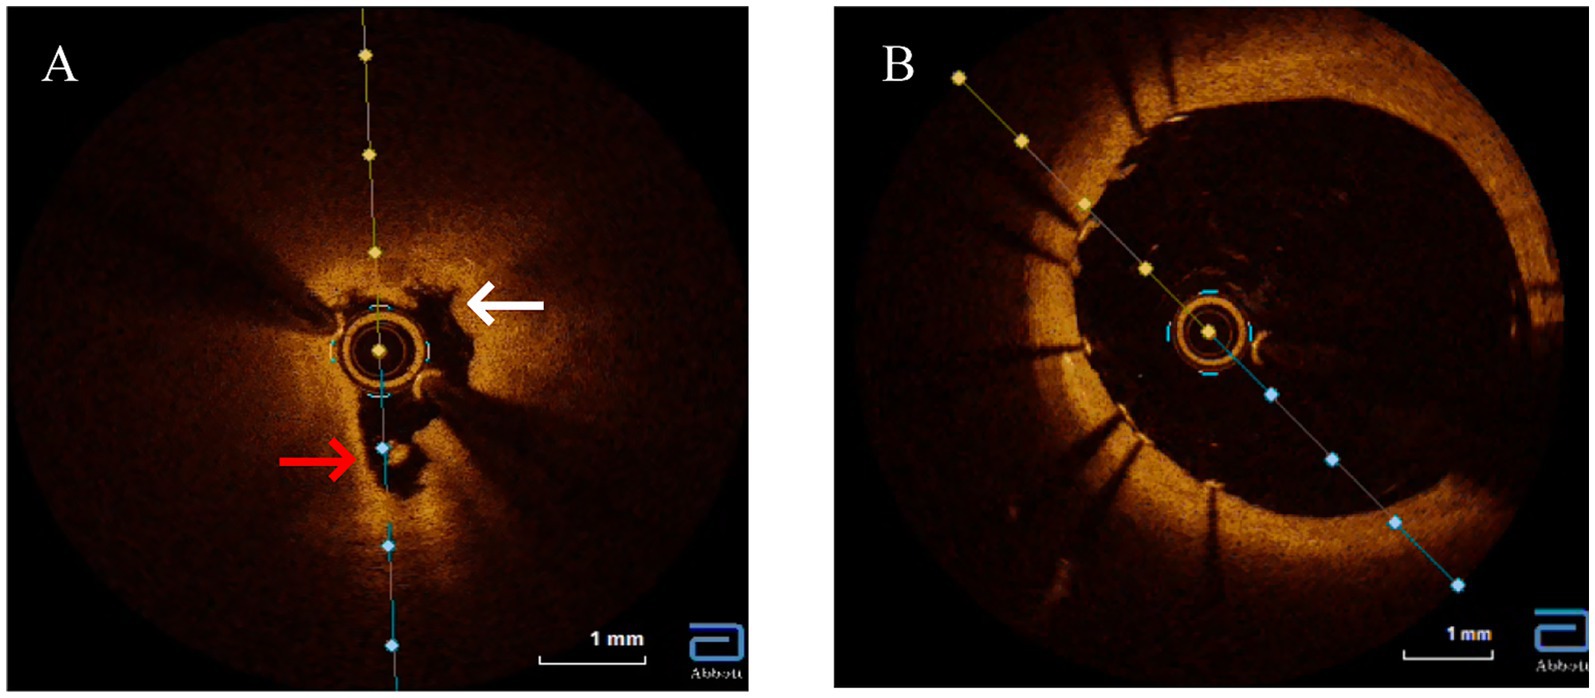

Given the constellation of ostial-predominant coronary disease, aortic aneurysm, and the profound discordance between angiographic severity and the objective lack of atherosclerosis (CACS = 0, normal CIMT, absence of traditional risk factors), an alternative etiology such as aortitis was strongly suspected. The positive TPPA test, indicating past or current Treponema pallidum infection, made cardiovascular syphilis the leading diagnostic consideration. To confirm or exclude this suspicion and to guide the optimal intervention, intravascular OCT was performed. Recognizing OCT’s unique capability to evaluate plaque morphology, composition, and stenosis etiology while assessing PCI risks, we opted for OCT-guided PCI rather than coronary artery bypass grafting (CABG) due to the focal ostial involvement and Rentrop grade 2 collateral circulation. OCT revealed severe ostial stenosis with medial layer disintegration, hyporeflective adventitial microcalcifications, and vasa vasorum obliteration (Figure 4A). Figure 4B showed stent implantation after PCI treatment. These features distinguished syphilitic vasculitis from atherosclerosis (which typically shows lipid-rich plaques) or Takayasu arteritis (diffuse intimal thickening).

Figure 4

Optical coherence tomography (OCT) imaging of the left main ostium. (A) Baseline OCT reveals features pathognomonic for syphilitic vasculitis, including severe luminal narrowing, marked disruption of the medial layer (white arrows), obliterated vasa vasorum appearing as signal-poor voids, and diffuse adventitial microcalcifications (red arrows). Crucially, key features of atherosclerosis, such as a lipid core or a distinct fibrous cap, are absent. (B) Post-intervention, showing a well-apposed stent and restoration of the vessel lumen.

Cardiovascular syphilis represents a late-stage complication of Treponema pallidum infection that continues to pose significant diagnostic challenges in contemporary practice (4). Typically manifesting 10–30 years after initial exposure, this condition predominantly affects the aorta, coronary ostia, and valvular structures, with classic presentations including aortitis, aortic regurgitation, and aneurysmal dilation (5). Our case illustrates a classic diagnostic dilemma of cardiovascular syphilis: proximal coronary stenosis. This dilemma was further compounded by serological ambiguity—a non-reactive RPR despite a positive TPPA—a pattern characteristic of late-stage disease due to immunological exhaustion (6). Given this ambiguity, our first critical step was to rule out alternative diagnoses, particularly atherosclerosis. In such clinically ambiguous scenarios, OCT emerges as a crucial diagnostic tool, providing detailed microstructural characterization when histopathological confirmation is unavailable (7). The OCT findings in our patient, including medial layer disruption, hyporeflective adventitial microcalcifications, and vasa vasorum obliteration, created a distinctive morphological signature differentiating syphilitic involvement from atherosclerotic disease or idiopathic aortitis. These features contrast sharply with the lipid-rich plaques with fibrous caps characteristic of atherosclerosis or the concentric laminar inflammation seen in giant cell arteritis, instead demonstrating fragmented elastic laminae and peri-adventitial scarring consistent with chronic ischemic injury from endarteritis obliterans (8). The absence of lipid pools or thrombus on OCT argued against acute plaque rupture, while the ostio-proximal localization with Rentrop grade 2 collateralization supported a slowly progressive inflammatory stenosis process (9). This case unequivocally underscores the limitation of relying solely on RPR in late-stage syphilis. A non-reactive RPR does not exclude active vasculitis, as evidenced by the positive TPPA and, crucially, the definitive OCT findings. This discrepancy, potentially reflecting the prozone phenomenon or a serofast state, underscores the necessity of a high clinical suspicion and the use of adjunctive imaging in such cases.

The diagnostic value of OCT extends to its ability to differentiate syphilitic vascular involvement from other vasculitides (10). While Takayasu arteritis typically presents with diffuse intimal thickening and homogeneous signal intensity, syphilitic lesions demonstrate irregular medial hyporeflectivity. Similarly, IgG4-related aortitis primarily shows adventitial fibrosis without the microcalcifications characteristic of syphilis, and atherosclerotic lesions exhibit features like thin-cap fibroatheromas and necrotic cores that are absent in syphilitic vasculopathy (11). Based on these observations, we propose three OCT hallmarks of cardiovascular syphilis: focal medial disintegration, adventitial microcalcifications, and obliterated vasa vasorum—though these findings require validation in larger patient cohorts. The OCT findings were pivotal, as they provided the definitive morphological evidence that confirmed our suspicion after we had systematically excluded atherosclerosis. Indeed, the most critical step in our diagnostic process was this systematic exclusion. Several key pieces of evidence converged to make atherosclerosis an unlikely cause for the patient’s complete left main ostial occlusion. First, the patient lacked major traditional risk factors, including smoking, hypertension, and diabetes. Second, and most powerfully, the coronary artery calcium score (CACS) was zero. CACS is a highly sensitive marker for the presence of coronary atherosclerosis, and a score of zero confers an extremely low probability of obstructive atherosclerotic disease. The severe, non-calcified ostial lesion in our patient is therefore highly atypical for an atherosclerotic origin. Third, the absence of atherosclerosis was a systemic finding, supported by a normal carotid intima-media thickness and the lack of plaques in other major arteries. Finally, the lesion’s location—perfectly confined to the coronary ostium, adjacent to a dilated aortic root—is a classic hallmark of syphilitic aortitis, which primarily affects the aortic media and adventitia, leading to secondary ostial narrowing. In contrast, atherosclerotic lesions are typically more diffuse and located distal to the ostium within the coronary artery itself (Table 1).